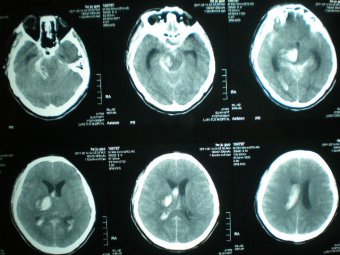

3月13日下午,我院急救中心接到120求救電話,家住濰城經(jīng)濟(jì)開發(fā)區(qū)邢石村的90歲老人玄大媽突發(fā)腦溢血, 出現(xiàn)呼吸不規(guī)整等癥狀,生命危在旦夕。 經(jīng)我院急診科緊急手術(shù)搶救,玄大媽脫離了生...

•   腦出血微創(chuàng)治療技術(shù) 日期:2015-12-29 10:34:00 點(diǎn)擊:1657 好評:29

2007年濰坊市市立醫(yī)院派急診科主任、副主任醫(yī)師劉樹森到北京301醫(yī)院進(jìn)修腦出血微創(chuàng)術(shù)。北京301醫(yī)院腦出血微創(chuàng)術(shù)技術(shù)居全國先進(jìn)水平。經(jīng)過半年進(jìn)修,劉樹森熟練掌握了腦出血微創(chuàng)治療術(shù)。2008年開始應(yīng)用北京301腦...